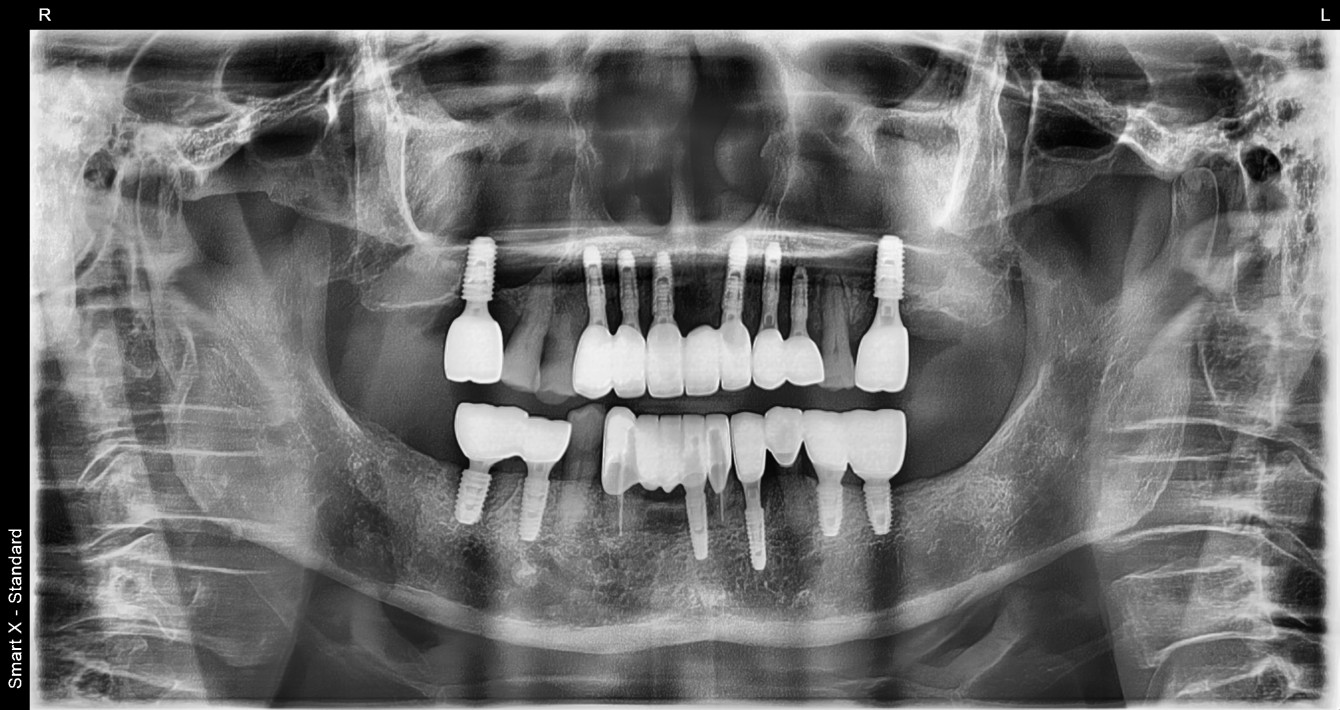

임플란트 | 전악재건 임플란트 케이스 입니다

환자명 이** 치료기간 5개월 한줄 설명 상하악 구치부 전치부를 포함한 전악 재건 임플란트케이스 입니다.